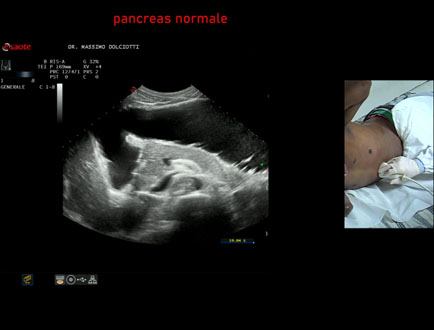

Data inserimento: 22/12/2023

Ecografia del: 30/11/2023

Strumento: Esaote MyLab Eight

Sonda: Convex Multifrequenza 1-8 MHz

Età Paziente: M 33 anni

Motivazione dell'esame: litiasi della colecisti.

Commento all'esame: le immagini ed il video documentano il fegato normale - segmentazione epatica, pancreas normale, colecisti con piccolo calcolo.

Conclusioni: segmentazione epatica, pancreas e colecisti con piccolo calcolo (liver segmentation, pancreas and gallbladder with small stone).

Presentazione: Dr. Massimo Dolciotti - Ancona

Elaborazione digitale: Andrea Dini - Ancona